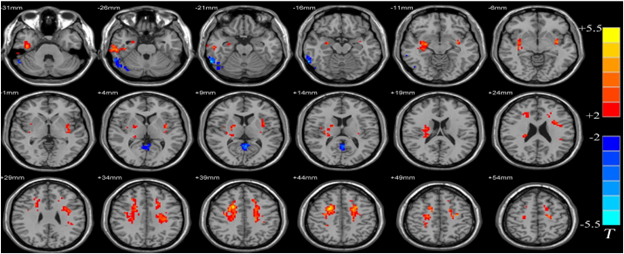

As the main purpose of the fMRI scan is to place brain activity in space (Beaulieu, 2016), it seems reasonable to focus on several spatial transformations initially. At first glance, one can see that the fMRI scan (either on the paper or on the screen) has a specific size. It means that the object of representation (e.g., the human brain) is ‘framed’ into the scan. Moreover, even though the representation proposes a high level of realism, the size of the brain on the screen does not coincide with the size of the brain in the patient’s head (Verbeek, 2008). Moreover, the human brain is represented on the scan in a specific perspective (see figure 1). In scientific literature, this perspective is usually named a ‘bird-eye perspective’13 (Rosenberger, 2020). Of course, such a perspective isn’t random or accidental but has functional purposes. The ‘bird-eye perspective’ provides the fMRI practitioner with a better ‘view’ of the human brain as a whole. From this perspective, practitioner can observe the human brain in its totality. This is what differs fMRI from other methods of brain study. Other techniques “make one small

The other observation about the transformative role of the fMRI scans is that some parts of the brain are highlighted with different colors while others are left in a ‘gray zone’. This happens because of the particular computer software, which allows an active interaction with the image data. The practitioner, for example, can “use the contrast between different shades of gray or can dynamically change the shades of gray to locate the pathology. This process is called windowing. The radiologist can also make comparisons by changing the contrast of gray in a particular region of the image through a process that is called leveling” (Prasad, 2005, p. 299). This effect mediates the practitioner’s attention, attracting his/her attention to the parts highlighted with the color and at the same time decreasing the practitioner’s attention from other parts of the brain (de Boer et al., 2020; Friis, 2008).